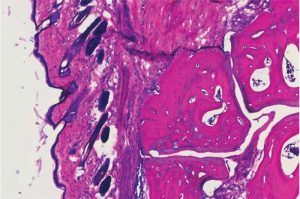

Emorragia cerebrale-Immagine Credit Public Domain- L’emorragia cerebrale e il sanguinamento nel tessuto cerebrale sono una condizione neurologica devastante che colpisce milioni di persone ogni anno. Ha un alto tasso di mortalità, mentre i sopravvissuti sono affetti da deficit neurologici a lungo termine. Non è stato trovato alcun farmaco per supportare il recupero del cervello dopo l’emorragia. […]